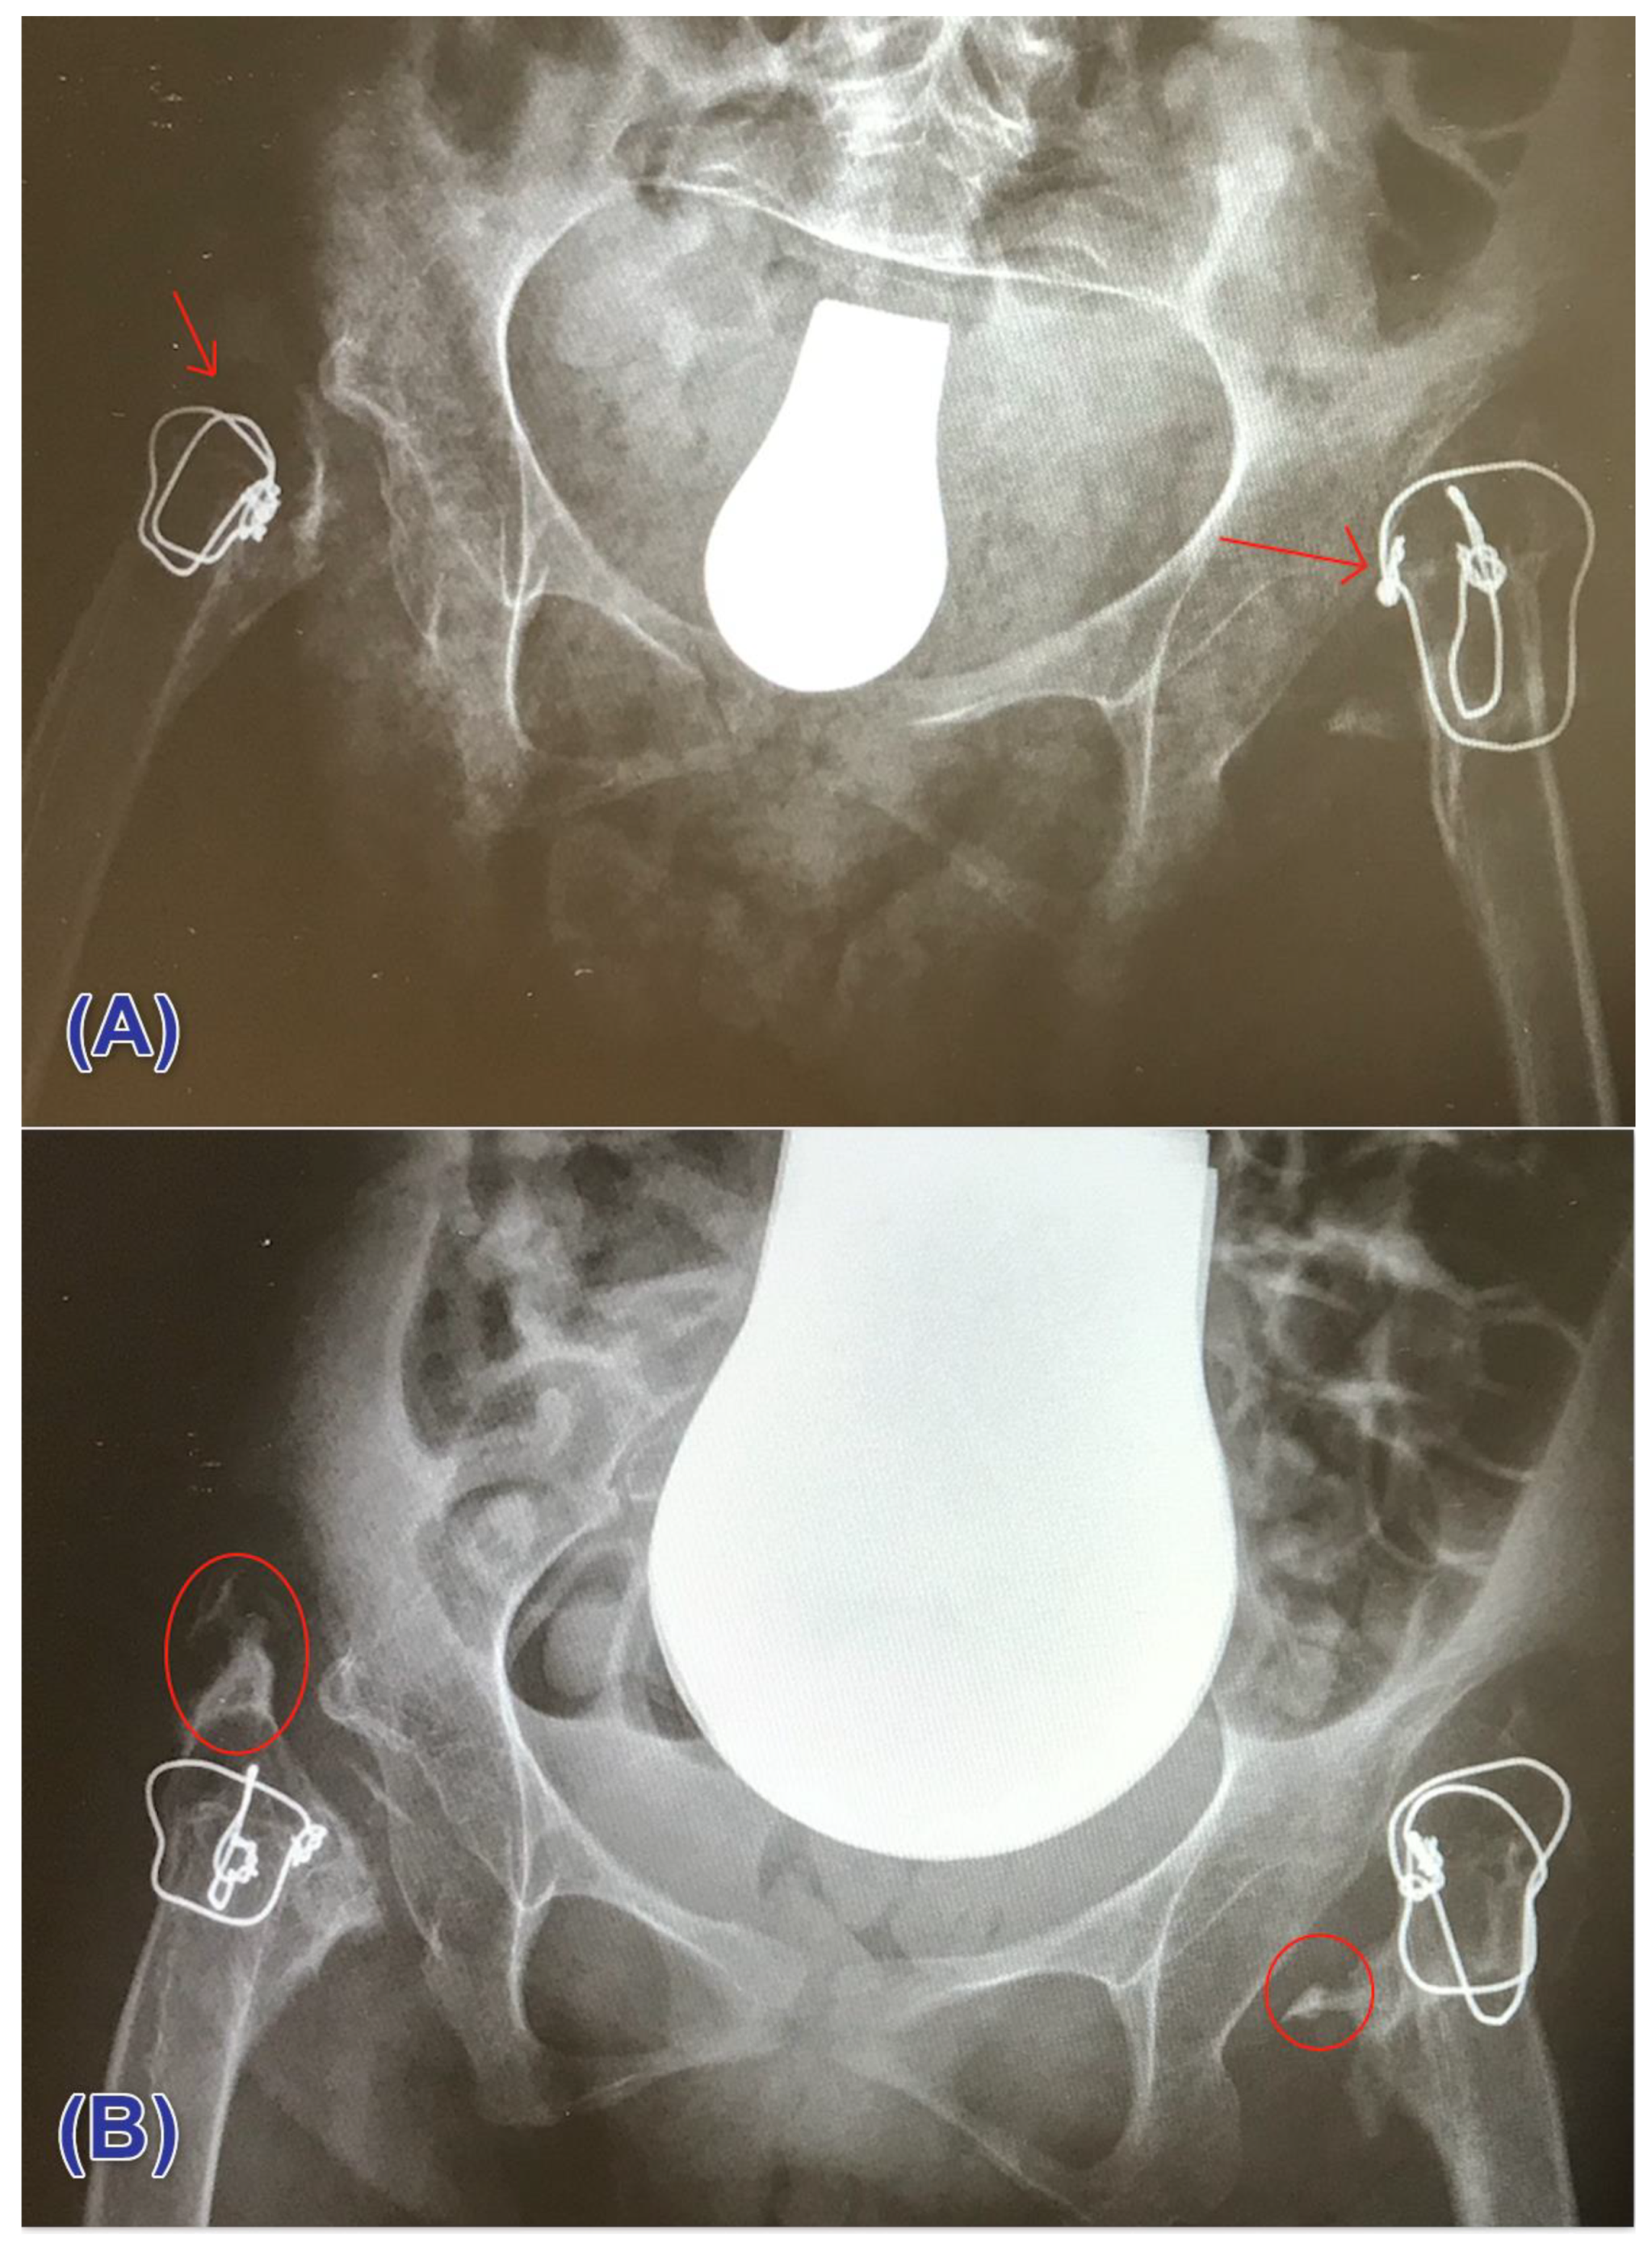

3.3. Heterotopic Ossification